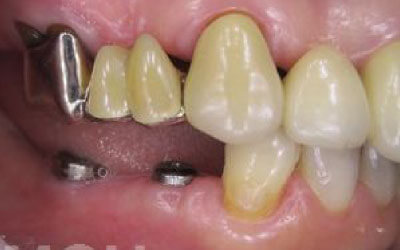

骨が薄い場合、そのままインプラントを行うのはお勧めできません。

ただし、事前に骨を増やす治療を行ったり、インプラントと同時に骨を増やす治療を行えば、インプラントは可能です。